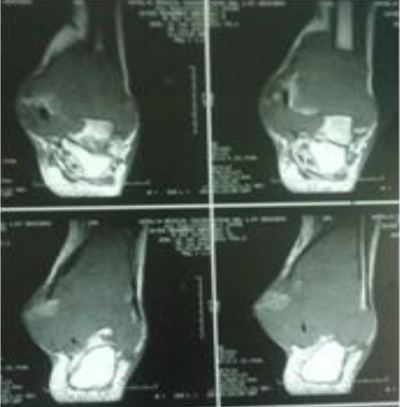

We report the case of a 37-year-old young man with no notable pathological antecedents who presented at the orthopedic consultation for a painful swelling of the left distal tibia and fibula that had been evolving for 5 months and without any alteration of the general state. There was change in color and consistency of the skin with respect to the tumor action. On physical examination, there was a dorsoflextion blockage of foot because of the large volume occupied by the tumor mass and the articular destruction at the level of the distal tibio-fibular joint; plantar flexion estimated at 10˚ and dorsal flextion at 3˚; inversion at 5˚ and eversion at 2˚. The x-ray showed a lesion with blurred boundaries, extending into the soft tissue that is not limited by a bony shell; with destruction of the cortex, invasion of soft parts and honeycomb pseudo-partitions (Figure 1-2). And finally the Magntic Resonant Imaging (MRI) of the left leg showed (Figure 3-4-5-6) a lysis of the cortex of the lower extremity of the leg. It corresponds to grade 3 of the Campanacci and Merled ’Aubignee classification. A complete surgical resection below knee amputation (BKA) was offered to the patient. Under spinal anesthesia, this incision was made proximally to expose a healthy portion of the leg bone. Surgical removal of the tumor by BKA a proximal resection of the tibia and fibular bone by about 2 cm in the healthy zone. The anatomopathological assessment (Figure 7) showed abundant mononuclear cells and discrete nuclear anomalies with marked mitotic activity, but without atypical forms. The histological examination of the bone fragments confirmed a grade 3 giant cell tumor according to Sanerkin, Jaffe Lichtenstein and Pottis. CT scan was done to exclude pulmonary metastases (Figure 8). At three weeks removal of suture and start physiotherapy of knee. Surgical treatment with the excision of the large tumor mass by BKA improved the function of the leg and general condition of the patient.

Figure 3: MRI report demonstrates heterogeneous lesion involve distal tibia and fibula.

Figure 4: MRI Show heterogeneous lesion involve distal tibia and fibula.

Figure 5: MRI Show heterogeneous lesion involve distal tibia and fibula with cortical break posteriomedially.

Figure 6: MRI Show heterogeneous lesion involve distal tibia and fibula with fatty infiltration and enhancement of blood vessel at medial site.